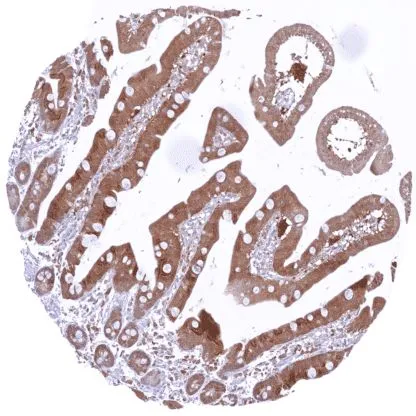

IHC-P analysis of human duodenum tissue using GTX639931 Caspase 3 antibody [HMV307] HistoMAX™.

A strong cytoplasmic caspase 3 positivity of epithelial cells.